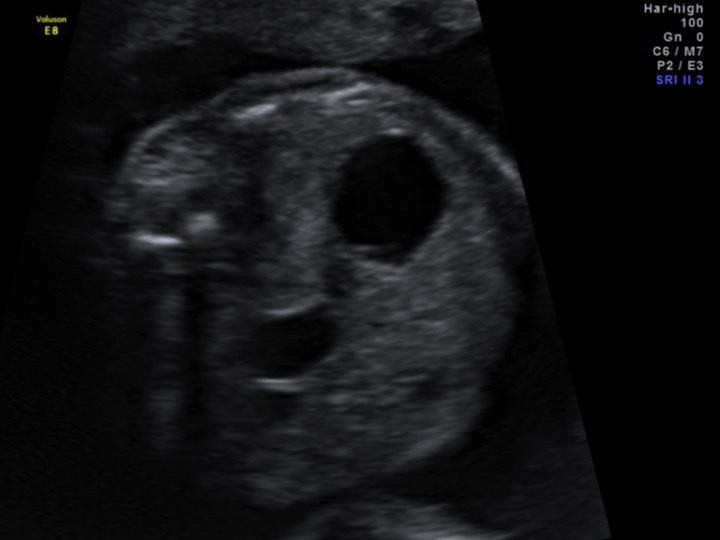

En la figura 1 se observa la presencia del signo de la doble burbuja.  Para confirmar este hallazgo es imprescindible que haya continuidad entre ambas burbujas (figura 2). El diagnóstico presuntivo en este caso es el de atresia duodenal y se asocia en aproximadamente un 30% de los casos a trisomía 21.

En el período prenatal el signo de la doble burbuja es un hallazgo característico. En un corte axial del abdomen fetal se observa una burbuja a la izquierda que corresponde al estómago y otra a la derecha que corresponde a la primera porción del duodeno. Sin embargo, este signo posee numerosas limitaciones.  En primer lugar no está libre de falsos positivos. Por otro lado, es infrecuente observarlo antes de las 20 semanas ya que recién cerca de las 25 semanas de gestación el estómago alcanza el 60% de la amplitud de presión del término. Por último, el vómito fetal puede descomprimir el estómago por lo que puede no ser visualizado. El polihidramnios se presenta hasta en un 70% de los fetos con atresia intestinal3,4.